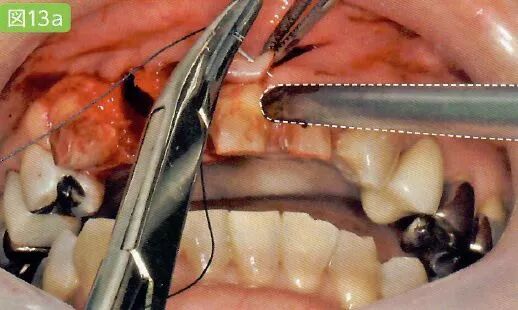

9缝合

切开的牙龈和牙槽粘膜用针缝合

用针缝合前吸引牙龈

缝合前用吸唾器吸引切开线区域。缝合后,结扎并截断缝合线前,吸引从切口结扎处溢出的血液。

缝合舌侧牙龈时,为了避免患者的舌头触碰到针尖,根据主治医生的喜好可以使用简易的吸唾器,对舌头进行排开。

结扎之后用吸唾器吸引

特别注意,吸引过程可能会引起结扎松动。